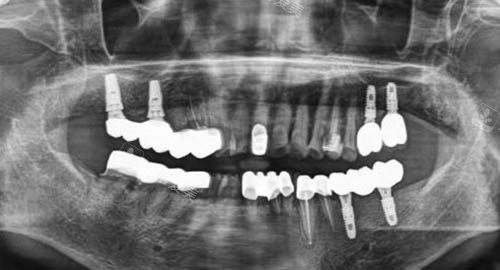

多颗牙齿种植ct

智能化种植借助靠前的设备和系统,能够更准一些地规划种植方案。

医生可以根据患者口腔的具体情况,如牙槽骨的密度、高度、宽度等,进行多方位的分析,从而确定较佳的种植位置和角度。

这样一来,种植体能够更稳固地植入,大大提高了种植的可行性。